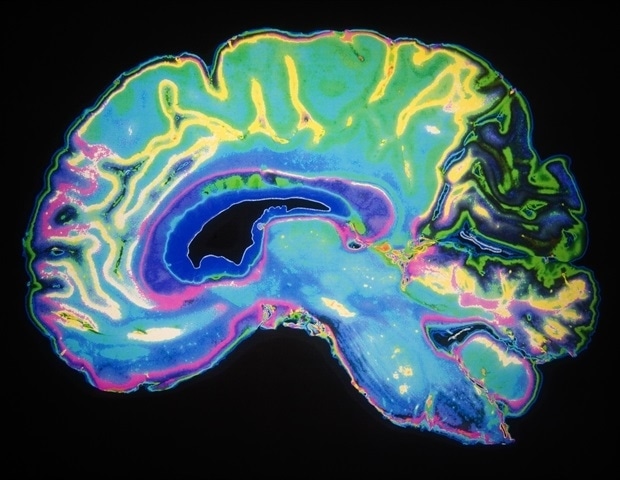

מעכבי אנהידראז פחמניים מראים הבטחה בהפחתת הצטברות חלבון טאו וניוון עצבי, וסוללים את הדרך לטיפולים חדשים במחלות נוירודגנרטיביות. לִלמוֹד: עיכוב